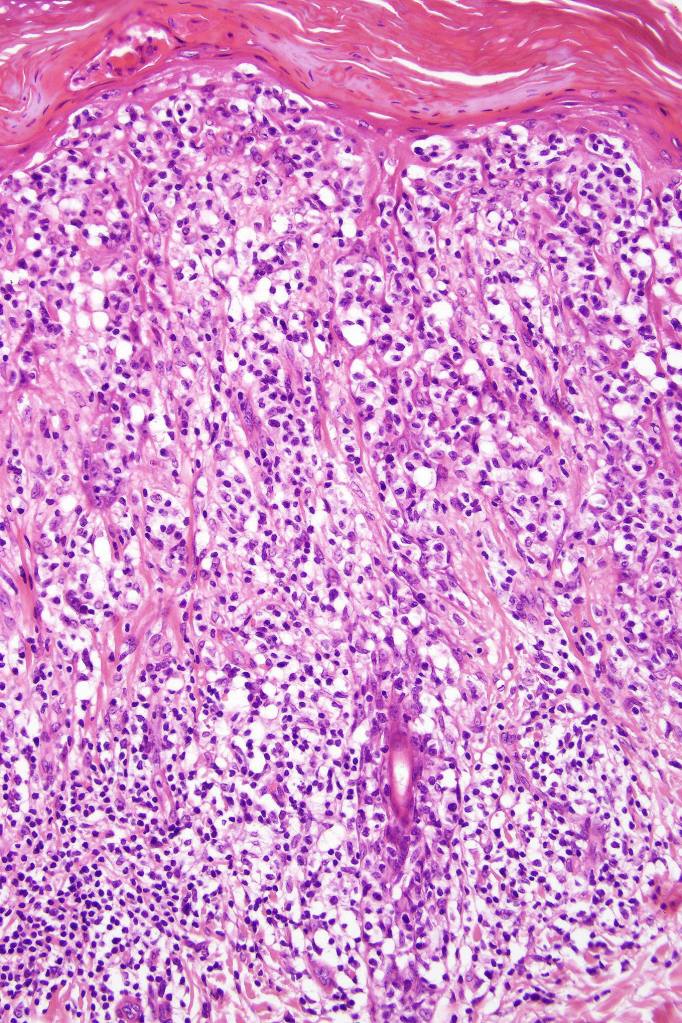

Histological features

•Hyperkeratosis/parakeratosis

•Acanthosis often psoriasiform

•Very marked epidermotropic infiltrate of atypical lymphocytes including Sézary cells

•Perinuclear halo often present

•Pautrier-like microabscesses

•Variable mitotic activity

•Superficial dermal perivascular lymphohistiocytic infiltrate with only sparse or absent atypical forms